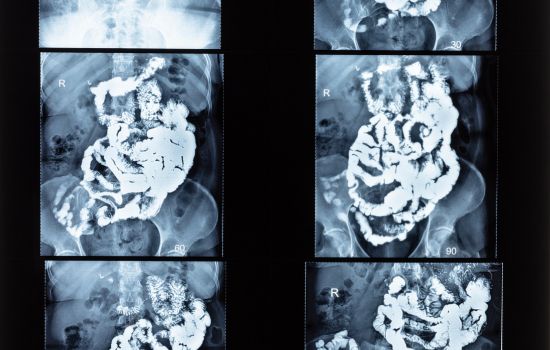

Die Gesundheit des Darms spielt eine zentrale Rolle für das allgemeine Wohlbefinden und die Lebensqualität. In unserer Kategorie „Darm“ finden Sie umfassende Informationen zu verschiedenen Darmbeschwerden und -erkrankungen und deren Herausforderungen. Diese reichen von weitverbreiteten Problemen wie Stuhlinkontinenz, Reizdarm und Verstopfung bis hin zu komplexeren Zuständen wie Darmentleerungsstörungen und Darmmanagement.

Erfahren Sie mehr über spezifische Krankheitsbilder wie Mastdarmvorfall (Rektumprolaps), Analfissuren und chronisch-entzündliche Darmerkrankungen. Wir bieten zudem detaillierte Einblicke in Hämorrhoiden und Divertikulose und Divertikulitis. Unser Ziel ist es, Ihnen fundiertes Wissen und praktische Tipps zu geben, um Ihre Darmgesundheit zu verbessern und Beschwerden effektiv zu lindern. Navigieren Sie durch unsere Themen und finden Sie wertvolle Ratschläge und Behandlungsansätze, die Ihrem Darm guttun.